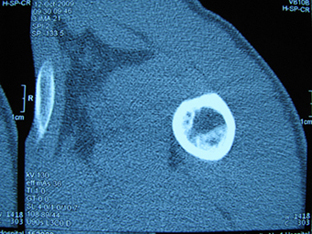

标题: X6404B:肱骨骨质破坏(CT片) [打印本页]

标题: X6404B:肱骨骨质破坏(CT片)

男,50岁,左肩部轻微疼痛,活动不便5个月就诊,近十天加重,无红肿热,间断理疗治疗无好转,既往5个月前左肩轻微拉伤史

骨巨?动脉瘤样骨囊肿?

内生软骨瘤。

内生软骨瘤。

内生软骨瘤?-----------

年纪大了,先要排除转移瘤。

髓腔内软组织肿块并斑片状钙化,考虑高分化软骨肉瘤可能性大。

考虑骨巨或动脉瘤样骨囊肿。

内生软骨瘤可能性大,期待结果。

孤立性骨囊肿。

内生软骨瘤可能性大

其内可见钙化,考虑软骨源性肿瘤,内生软骨瘤可能

但由于年龄较大,恶性软骨肉瘤待排

肱骨头内巨大软组织肿块并斑片状钙化,内生软骨瘤?骨巨细胞瘤?软骨粘液样纤维瘤?期待结果!

髓腔内软组织肿块并斑片状钙化,考虑高分化软骨肉瘤可能性大。

内生软骨瘤可能性大

肱骨头内巨大软组织肿块并斑片状钙化,内生软骨瘤?骨巨细胞瘤?软骨粘液样纤维瘤?期待结果

考虑内生软骨瘤?骨巨细胞瘤?

内生软骨瘤?骨巨细胞瘤?

先要排除转移瘤。